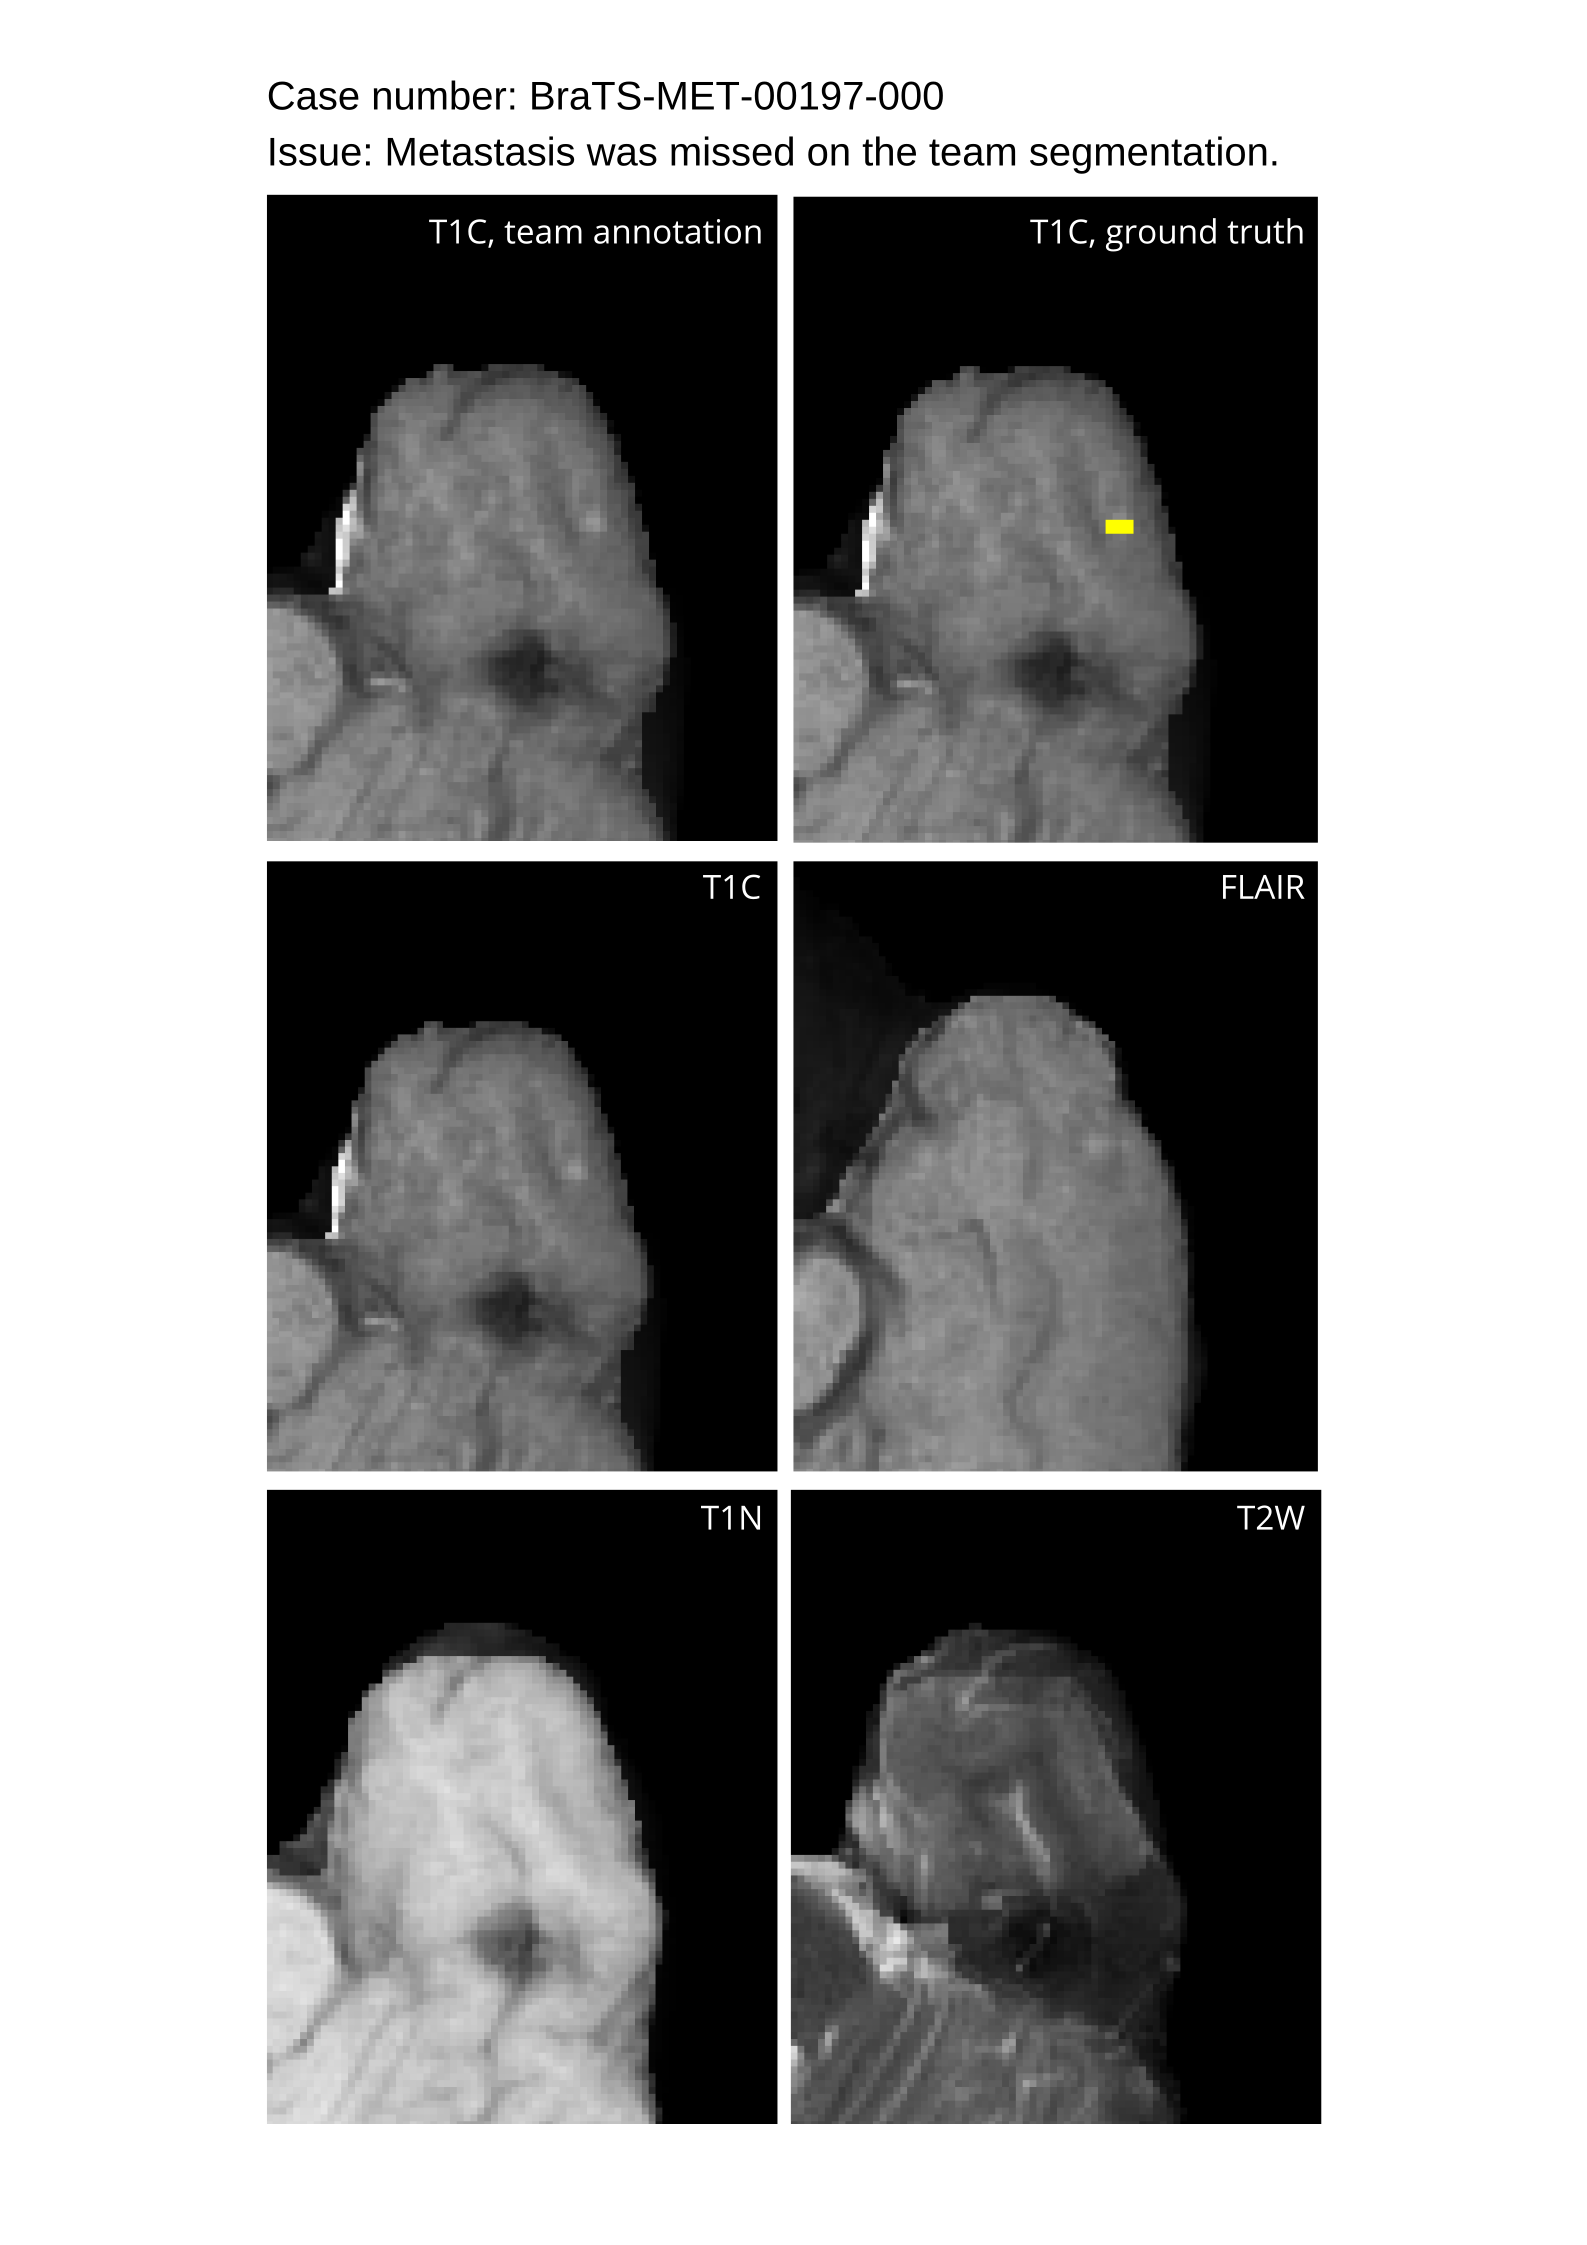

4.9 Common Errors of Automated Segmentations

Based on observations from previous BraTS challenges, common errors in automated segmentations were identified. The most typical errors in the current challenge included:

1. 1.

Automated algorithms missing small metastases. Enhancing metastasis was fused using the minority voting algorithm to aggregate all enhancing tumor voxels identified by the three algorithms. However, many small metastases were missed and were manually segmented by neuroradiology attendings.

2. 2.

Segmentation of white matter changes from microvascular disease. Peritumoral edema segmentations were checked by neuroradiology attendings and modified.

3. 3.

The segmentation of non-enhancing lesions that have intrinsic T1 hyperintensity. Voxels with intrinsic T1 hyperintensity were manually removed from ET segmentations.

These insights led to specific adjustments in the annotation process to enhance accuracy.